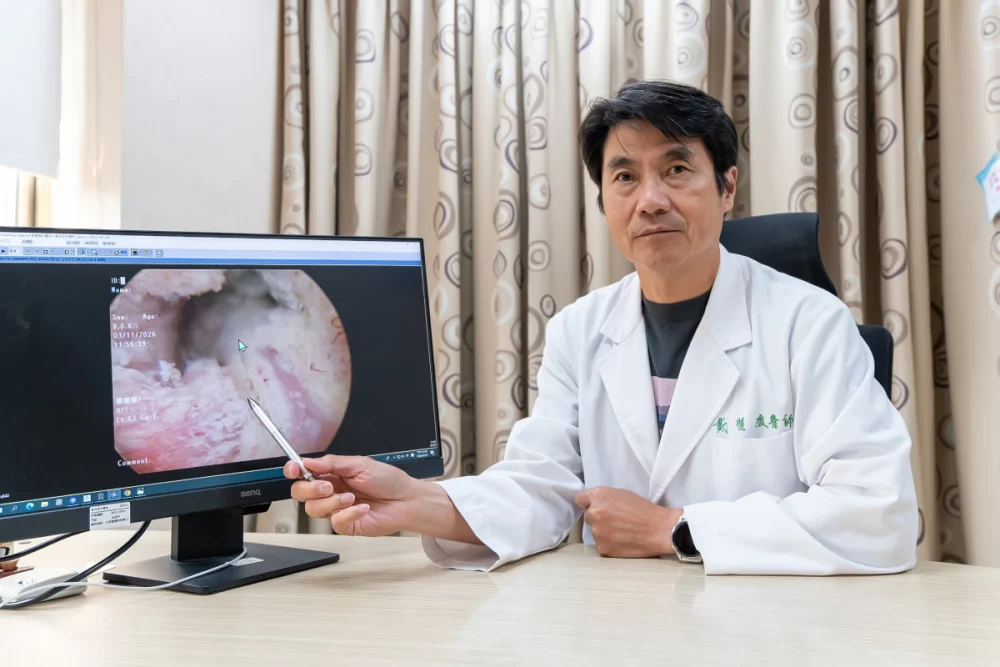

揮別攝護腺癌 「海扶刀」精準定位消融癌細胞

記者季大仁/新竹報導東元醫院泌尿外科戴順慶醫師利用「海扶刀(HIFU)高強度聚焦超音波微創手術」幫助多名攝護腺癌病人,揮別早期攝護腺癌症陰霾。攝護腺癌呈現年輕化,正值壯年的病人而言,如何在根除癌症的同時保留生活品質是關鍵。東元綜合醫院泌尿外 …